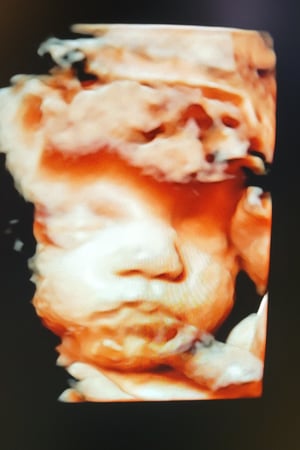

Tasha Crump, is registered by the American Registry of Diagnostic Medical Sonographers (ARDMS) and have over 18 years experience in medical diagnostic sonography specializing in Maternal Fetal Medicine. She is a highly proficient in the art of 3D 4D ultrasound. Tasha has practiced and trained in NYC's top ranked hospitals including Columbia Presbyterian. At Love at First Sight Imaging Studio you'll be in a very comfortable and calming atmosphere for you and your family to bond with your baby. We have state of the art equipment with HD Live to image unbelievably realistic views of your baby. You will fall in Love at First Sight.